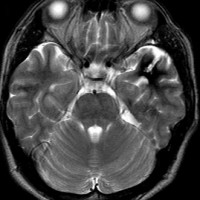

出血が溶けて少し小さくなっています。海綿状血管腫の周りには黒い縁取りがあります。この黒い部分は血液が溶けて残った鉄が脳の中にたまったことを示しています(siderosisといいます)。この鉄のしみ込みはけいれんの原因になると考えられます。この海綿状血管腫は中等度の大きさですが,治療が難しいほどのてんかんが無ければ手術などしないでほっておいてもいいです。手術で側頭葉(特に海馬)を損傷すると記憶の障害などもでます。